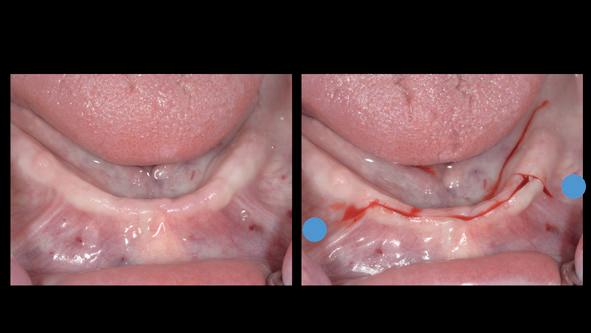

Verticaal botverlies & korte implantaten - De resorptie treedt soms overwegend verticaal op, waardoor de processus alveolaris geheel verdwijnt en er slechts een minimale hoeveelheid basaal/ residuaal bot overblijft. In de mandibula kan dit leiden tot een zeer lage kaak, met mediane kaakhoogtes tot nog maar 4-5 mm (potlood dikte!). Voorheen werd hier een transmandibulair implantaat geplaatst, omdat werd geanticipeerd op breuk [Powers et al, 1994], of werd gekozen voor het verticaal opbouwen van de mandibula: de klassieke absolute kaakverhoging. Tegenwoordig wordt het plaatsen van twee of vier korte implantaten met een lengte van slechts 4-8 mm beschouwd als een goed alternatief voor een augmentatie van de onderkaak (afbeelding 2). Dit scheelt aanmerkelijk in de belasting van de patiënt (minder ingrepen, geen narcose, kortere behandelduur, minimale morbiditeit) en levert goede resultaten op [Vazouras K et al, 2020; Telleman G, et al. 2013; Renouard F and Nisand D. 2006; Guljé F et al. 2012]

Horizontaal botverlies en mini-implantaten - Een geheel andere anatomische situatie ontstaat bij een meer horizontaal resorptiepatroon. Hierbij blijft de kaakhoogte vrijwel volledig intact, maar neemt de dikte van de processus alveolaris af tot een minimum van slechts enkele millimeters. Indien sprake is van een dergelijke zeer dunne processus alveolaris in de maxilla of mandibula, kan ervoor worden gekozen om gebruik te maken van mini-implantaten (implantaten met een diameter < 2.5 tot 3 mm, afbeeldingen 3a-b), als alternatief op een chirurgische kaakverbreding door middel van ‘buccal plating’ met een autoloog bottransplantaat. Het gebruik van mini-implantaten bespaart de patiënt pre-implantologische chirurgie, lange behandelduur, morbiditeit en de noodzaak tot herhaalde aanpassingen van de prothese. Door mini-implantaten flapless te plaatsen wordt de morbiditeit tot een minimum gereduceerd. Hiervoor is echter wel 3D-planning vooraf een vereiste alsook statische navigatie bij het plaatsen door middel van een dwingende boormal, vanwege de zeer geringe marges (zie casus, afbeeldingen 4a-q ). Een bijkomend voordeel van mini-implantaten is, dat ze uit één geheel bestaan en standaard zijn voorzien van

4a. Navigatie chirurgie met een dwingende boormal

4b. Na plaatsen wordt de boormal gefixeerd met ‘anchor pins’

4c. Voor mini-implantaten hoeft slechts één keer te worden geboord

4d. Uitnemen boormal na het ‘blind’ prepareren van het implantaatbed

een drukknopje. Hierdoor kan in een laatste levensfase eenvoudig nog een overkappingsprothese worden aangepast of vervangen, ook wanneer er geen aanvullende informatie meer beschikbaar is over het implantaatmerk, type en diameter. Mini-implantaten laten goede succes- en overlevingspercentages zien [Bidra en Almas 2013; Shatkin 2012; vanDoorne et al 2020; vanDoorne et al 2021]

4e. Mini-implantaat (Southern Implants, ILZ12D), diameter 2.4 mm

4f. Flapless plaatsen van het 1e implantaat

4g. Door het genavigeerd prepareren is het plaatsen van de implantaten kinderlijk eenvoudig

4h. Direct postoperatief na flapless aanbrengen van 6 mini-implantaten